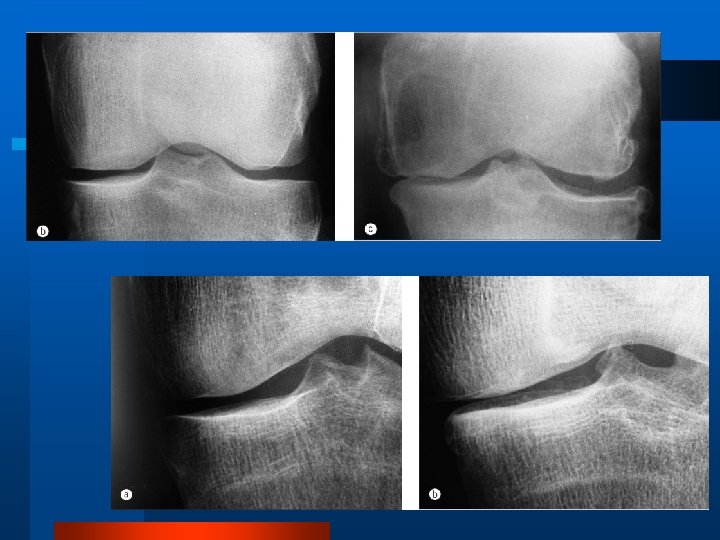

Examenul radiologic l Radiografia simplă este cel mai util mijloc imagistic în artroză, atât pentru diagnostic, cât şi pentru urmărirea evoluţiei. Aspectul l Îngustarea spaţiului articular l Scleroză subcondrală l Osteofitoză marginală l Pseudochisturi sau geode

Gradarea Kellgren-Lawrence 0: Normal I: Osteofite posibile şi posibil pensarea spaţiului articular II: Osteofite definite şi posibil pensarea spaţiului articular III: Osteofite moderate multiple, pensarea definită a spaţiului articular, scleroză şi posibil deformare a conturului osos IV: Osteofite mari, pensarea marcată a spaţiului articular, scleroză severă, şi deformare definită a conturului osos

Criterii de Diagnostic Gonartroza (artroza genunchiului) 1. 2. 3. 4. 5. 6. Dureri în genunchi în majoritatea zilelor pe parcursul lunii precedente Existenţa osteofitelor marginale în articulaţie Analiză lichidului sinovial, caracteristică pentru OAD Vârsta ≥ 40 ani Redoarea matinală ≤ 30 min. Cracment articular la mişcări active Diagnosticul OAD se stabileşte în baza existenţei punctelor 1 şi 2 sau punctelor 1, 3, 5 şi 6 sau punctelor 1, 4, 5 şi 6. Sensibilitate 94 %, specificitate 88 %.